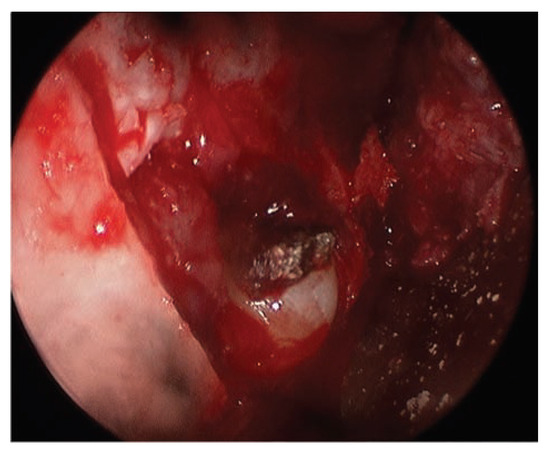

Report of a Case

![]() |